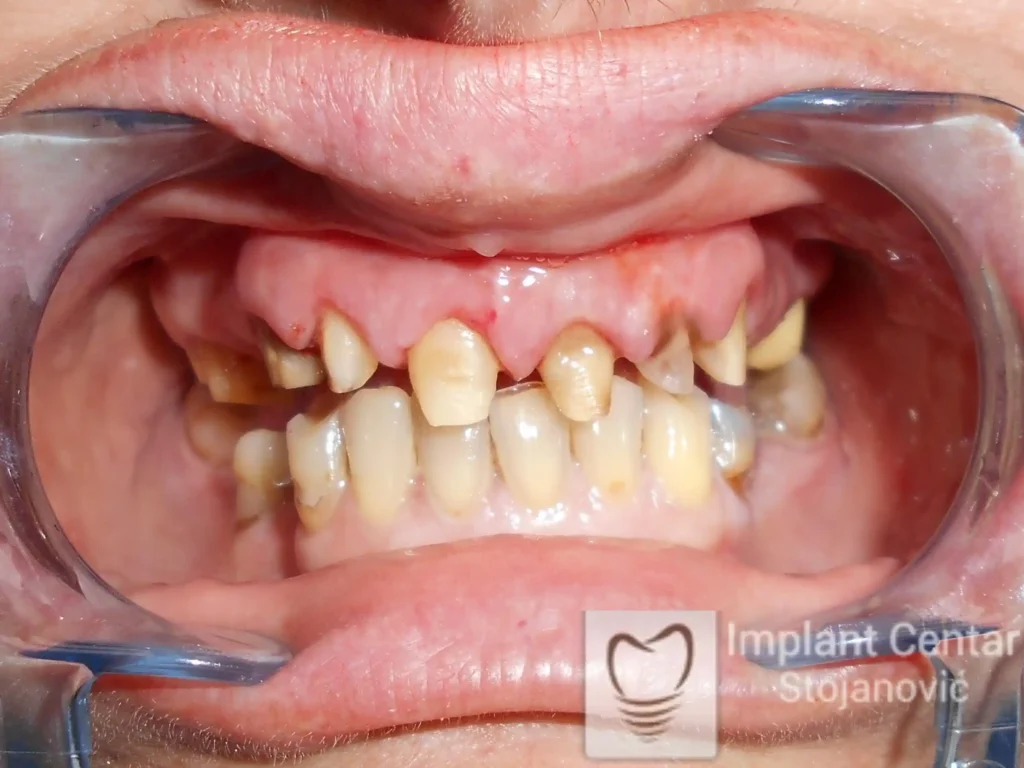

Na slikama 1, 2, 3 , 4  i  5 prikazan je izgled pacijenta pre početka terapije. Nakon detaljne kliničke i radiološke analize, doneta je odluka o vađenju zuba loše biološke vrednosti, dok su bezuba polja sanirana ugradnjom dentalnih implantata.

Nakon ugradnje implantata i pripreme preostalih zuba, pacijentu su izrađene fiksne privremene krunice, čime je postignut eugnatan zagriz već nakon jednog dana (slika 8, 9 i 10). Tokom perioda osteointegracije, pacijent se postepeno privikavao na novi položaj vilica i zagriz.

Po završetku perioda integracije, izrađeni su definitivni cirkonijum-keramički mostovi, čime je postignuta potpuna rekonstrukcija zagriza, kao i značajno poboljšanje estetike i oralne funkcije (slika 12, 13, 14 i 15).